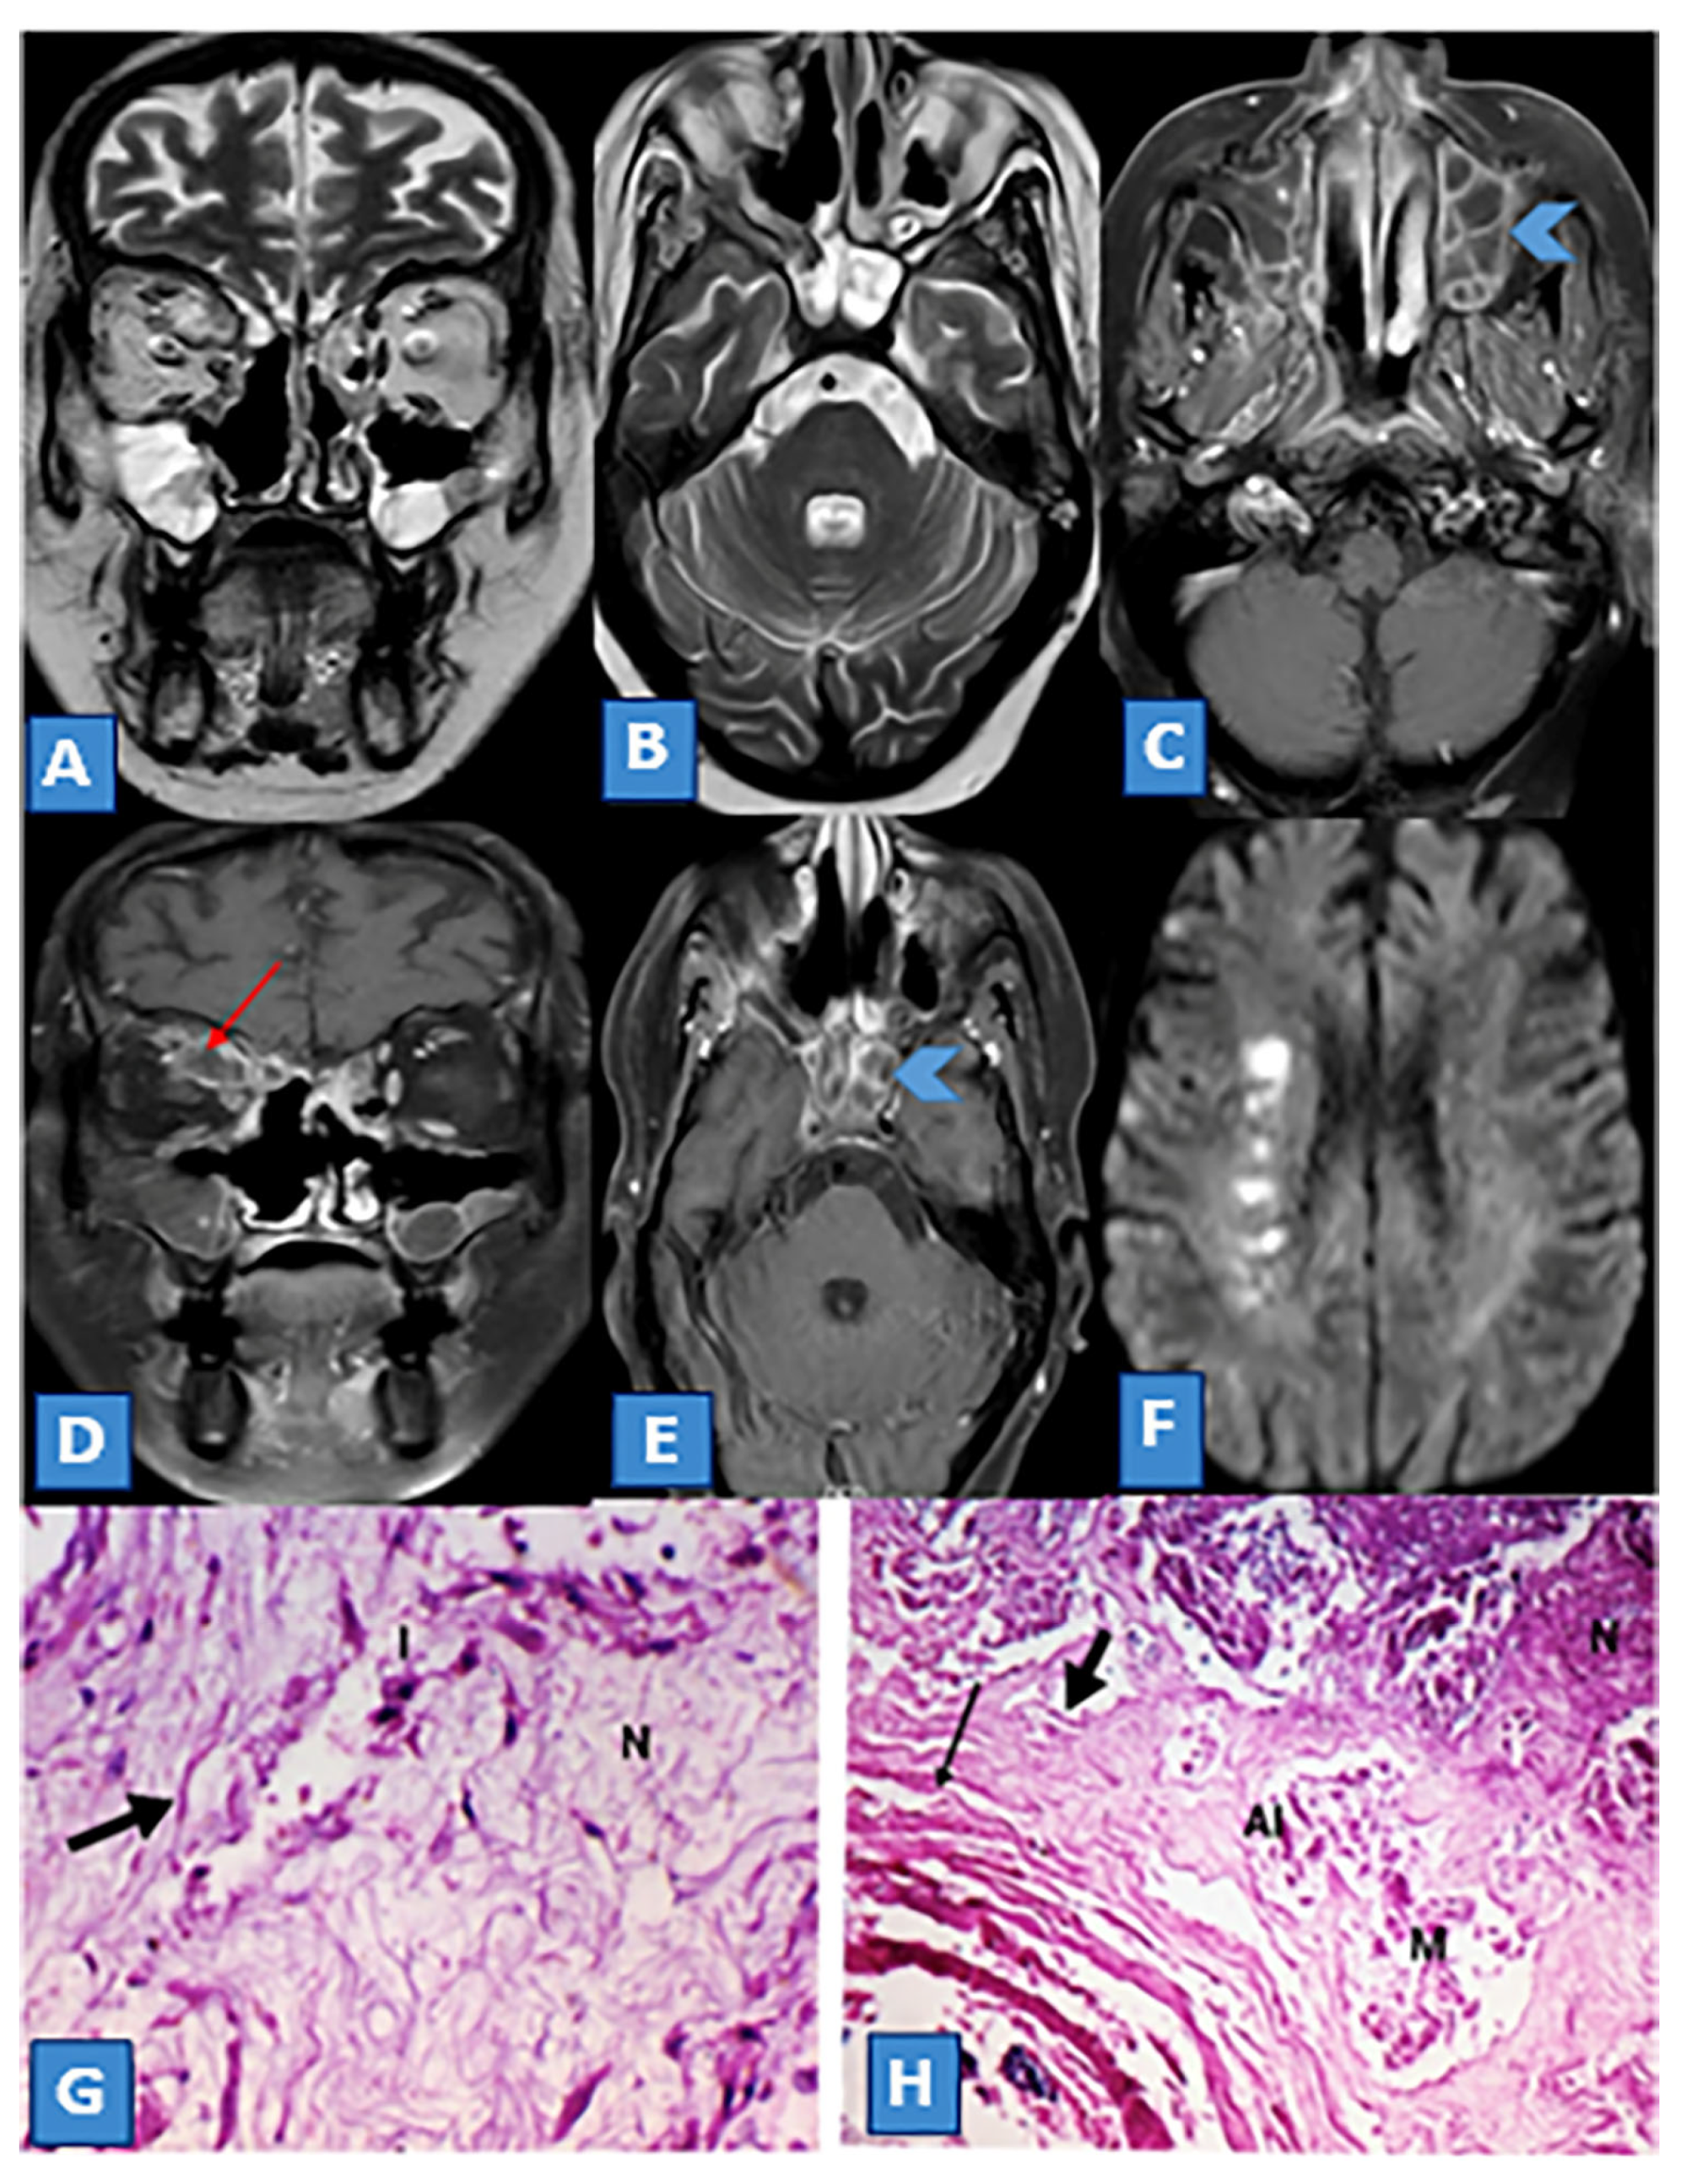

3.4. Extrasinus Extension

3.5. Histopathological Findings